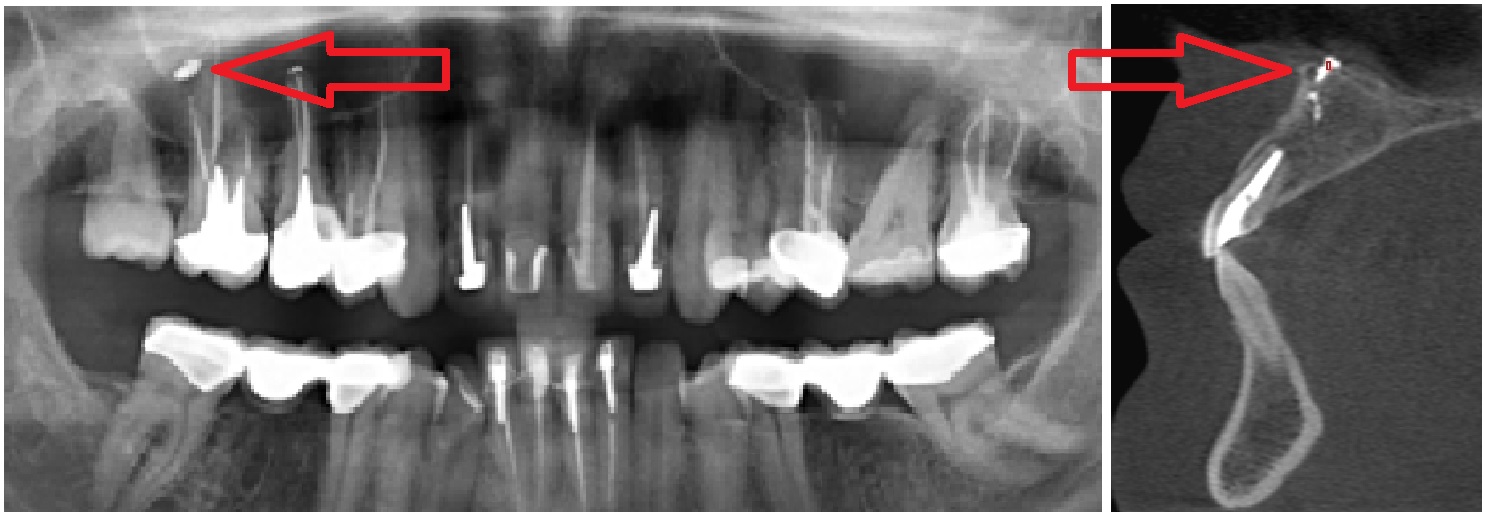

Стрелками показаны фрагменты пломбировочного материала (вид спереди и сбоку), который при пломбировании канала выпал за пределы зуба и «упёрся» в область залегания ветви тройничного нерва. У пациента долго болел зуб после лечения пульпита, затем онемела верхняя губа и часть щеки.

2.Рентгеновские исследования. На обычных рентгенограммах и панорамных снимках не всегда видна истинная картина болезни. Мы рекомендуем конусно-лучевую компьютерную томографию с функцией защиты от дефектов изображения от пломбировочного материала и протезов.